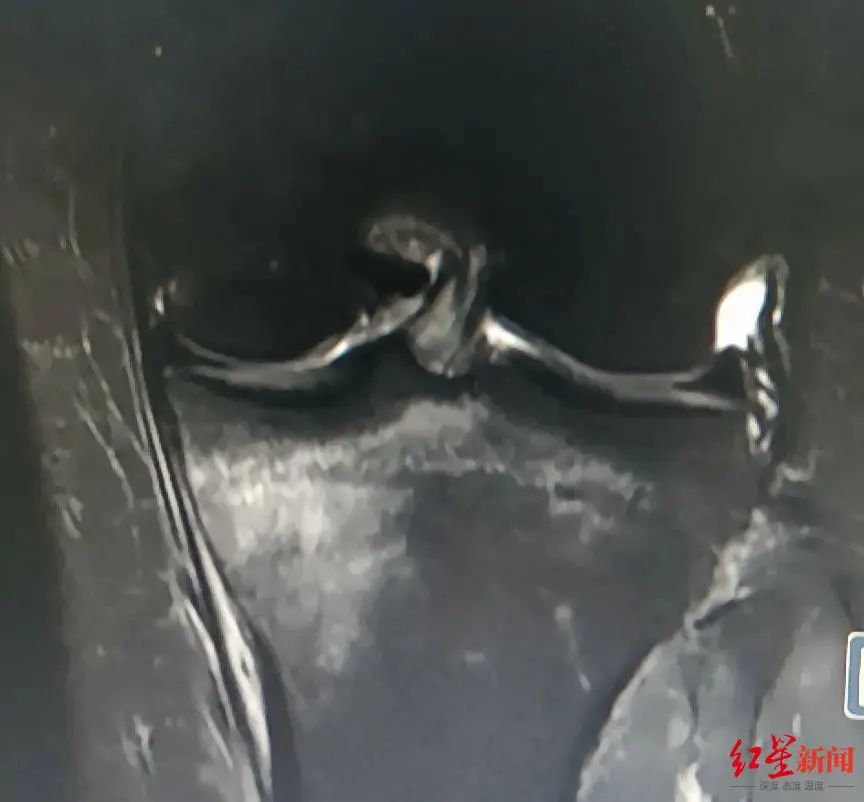

▲丁女士胫骨上端疲劳骨折图。

丁女士起初怎么都不敢相信这个结果,后经膝关节核磁共振检查明确。